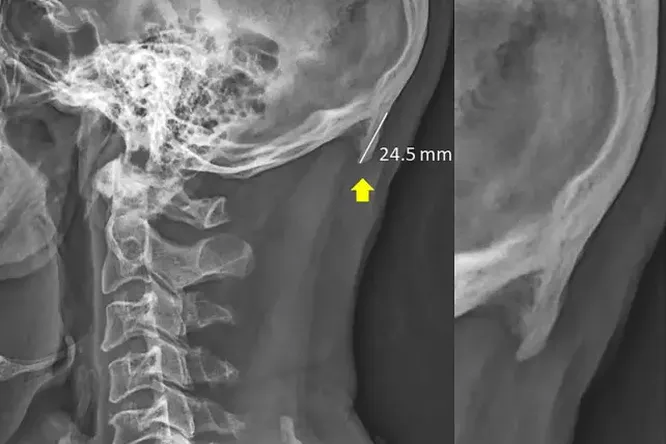

Примеры Джейка Бойла подтверждают тот факт, что наклон головы, характерный для всех пользователей смартфонов, провоцирует негативные последствия для здоровья, которые потом сложно исправить. Так, в медицинской практике стали встречаться случаи необычного заболевания, которое, как утверждают ученые, тоже является последствием скроллинга соцсетей. Доктор в области биомеханики из Университета Саншайн-Коста Дэвид Шахур (David Shahur) утверждает, за последнее десятилетие он все чаще видит пациентов со странным роговым наростом на затылке. Причем эти «рога» бывают такими большими, что их можно почувствовать через кожу.Впервые феномен «наружного затылочного бугра» описал французский ученый в 1885 году. Однако до настоящего времени эта патология была настолько редка, что исследователи не уделяли ей должного внимания.

В 2016 году Шахур и его коллеги разместили на ресурсе Wiley Research DE&I исследование, посвященное этому явлению. Проанализировав порядка 200 рентгеновских снимков, ученые выяснили, что растущие из черепа рога чаще встречаются у молодых мужчин, которые часто наклоняют голову вниз, чтобы посмотреть в экран смартфона. В результате на затылочную область, где мышцы шеи соединяются с черепом, оказывается дополнительное давление. Чтобы компенсировать нагрузку, поддерживая и без того тяжелую голову (у взрослых она весит около 4,5 кг), организму приходится наращивать новую костную ткань, которая помогает перераспределять вес. Это и приводит к появлению явно выраженных «рогов». Научные сотрудники отмечают: наросты не представляют серьезной опасности, но если они уже появились, избавиться от них не представляется возможным.

Несмотря на предварительные заключения, ученому сообществу еще предстоит провести ряд фундаментальных исследований, чтобы связать появление выступов на черепе с определенной частотой наклонов головы и временем, проведенным со смартфоном в руках. Пока выводы о прямой связи «рогов» с гаджетами остаются на уровне гипотез.